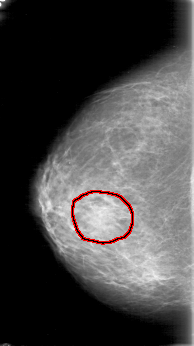

RIGHT_MLO LINES 5281 PIXELS_PER_LINE 3211 BITS_PER_PIXEL 12 RESOLUTION 43.5 OVERLAY

FILE: D_4023_1.RIGHT_MLO.OVERLAY

TOTAL_ABNORMALITIES 1

ABNORMALITY 1

LESION_TYPE MASS SHAPE OVAL MARGINS OBSCURED

ASSESSMENT 0

SUBTLETY 2

PATHOLOGY BENIGN

TOTAL_OUTLINES 1

BOUNDARY